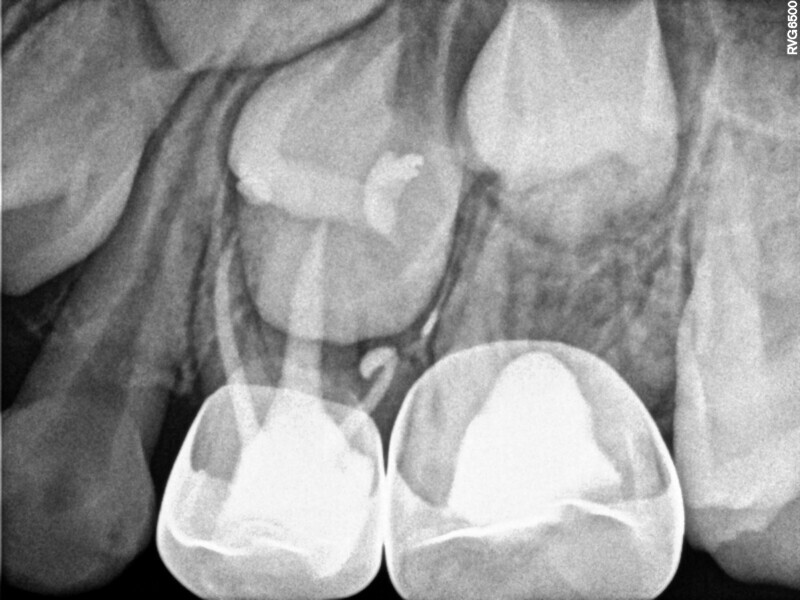

Cas 1 (Figs 1-4)

Cette patiente âgée de 4 ans et 7 mois présentait une douleur qui affectait la seconde molaire temporaire inférieure droite depuis plusieurs jours. L’examen clinique a révélé un gonflement du versant vestibulaire de la gencive et un œdème facial, ainsi qu’une carie occlusale profonde.Un diagnostic de nécrose pulpaire et d’abcès apical symptomatique ayant été posé, un traitement a été prescrit à la patiente, afin de maîtriser l’infection aiguë, et un nouveau rendez-vous a été fixé après l’antibiothérapie. Lors du deuxième rendez-vous, elle ne présentait plus aucune douleur et l’abcès buccal s’était partiellement résorbé. Il a été décidé de procéder à une pulpectomie et à la restauration de la dent. Dans ce cas, la dent présentait une extrusion excessive de matériau d’obturation. Après 15 mois, la réévaluation a confirmé l’absence de signes cliniques ou radiologiques pathologiques, et une apposition osseuse était visible dans la zone de la furcation.